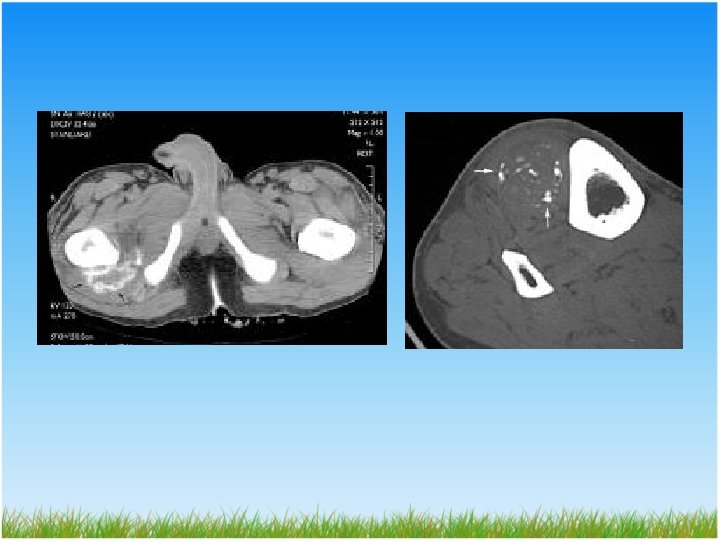

TANI Bilgisayarlı Tomografi(BT) – – – HO’nun lokalizasyonunu, Genişliğini, Çevre kas, damar, sinirlerle ilişkisini Olgunlaşmanın tamamlanma sınırlarını Bunlara göre operasyonun yönlendirilmesini sağlar

TANI Magnetik rezonans(MR) – Rutinde HO tanısında kullanılmaz – Tipik MR görüntüsü çerçeve şeklinde düşük sinyal intesidir. – Operatif yaklaşımı planlamak amaçlı kullanılabilir. – İntravenöz gadolonyum verilirse erken tanıda yararlı olabilir

n. iskiadikus Matür HO